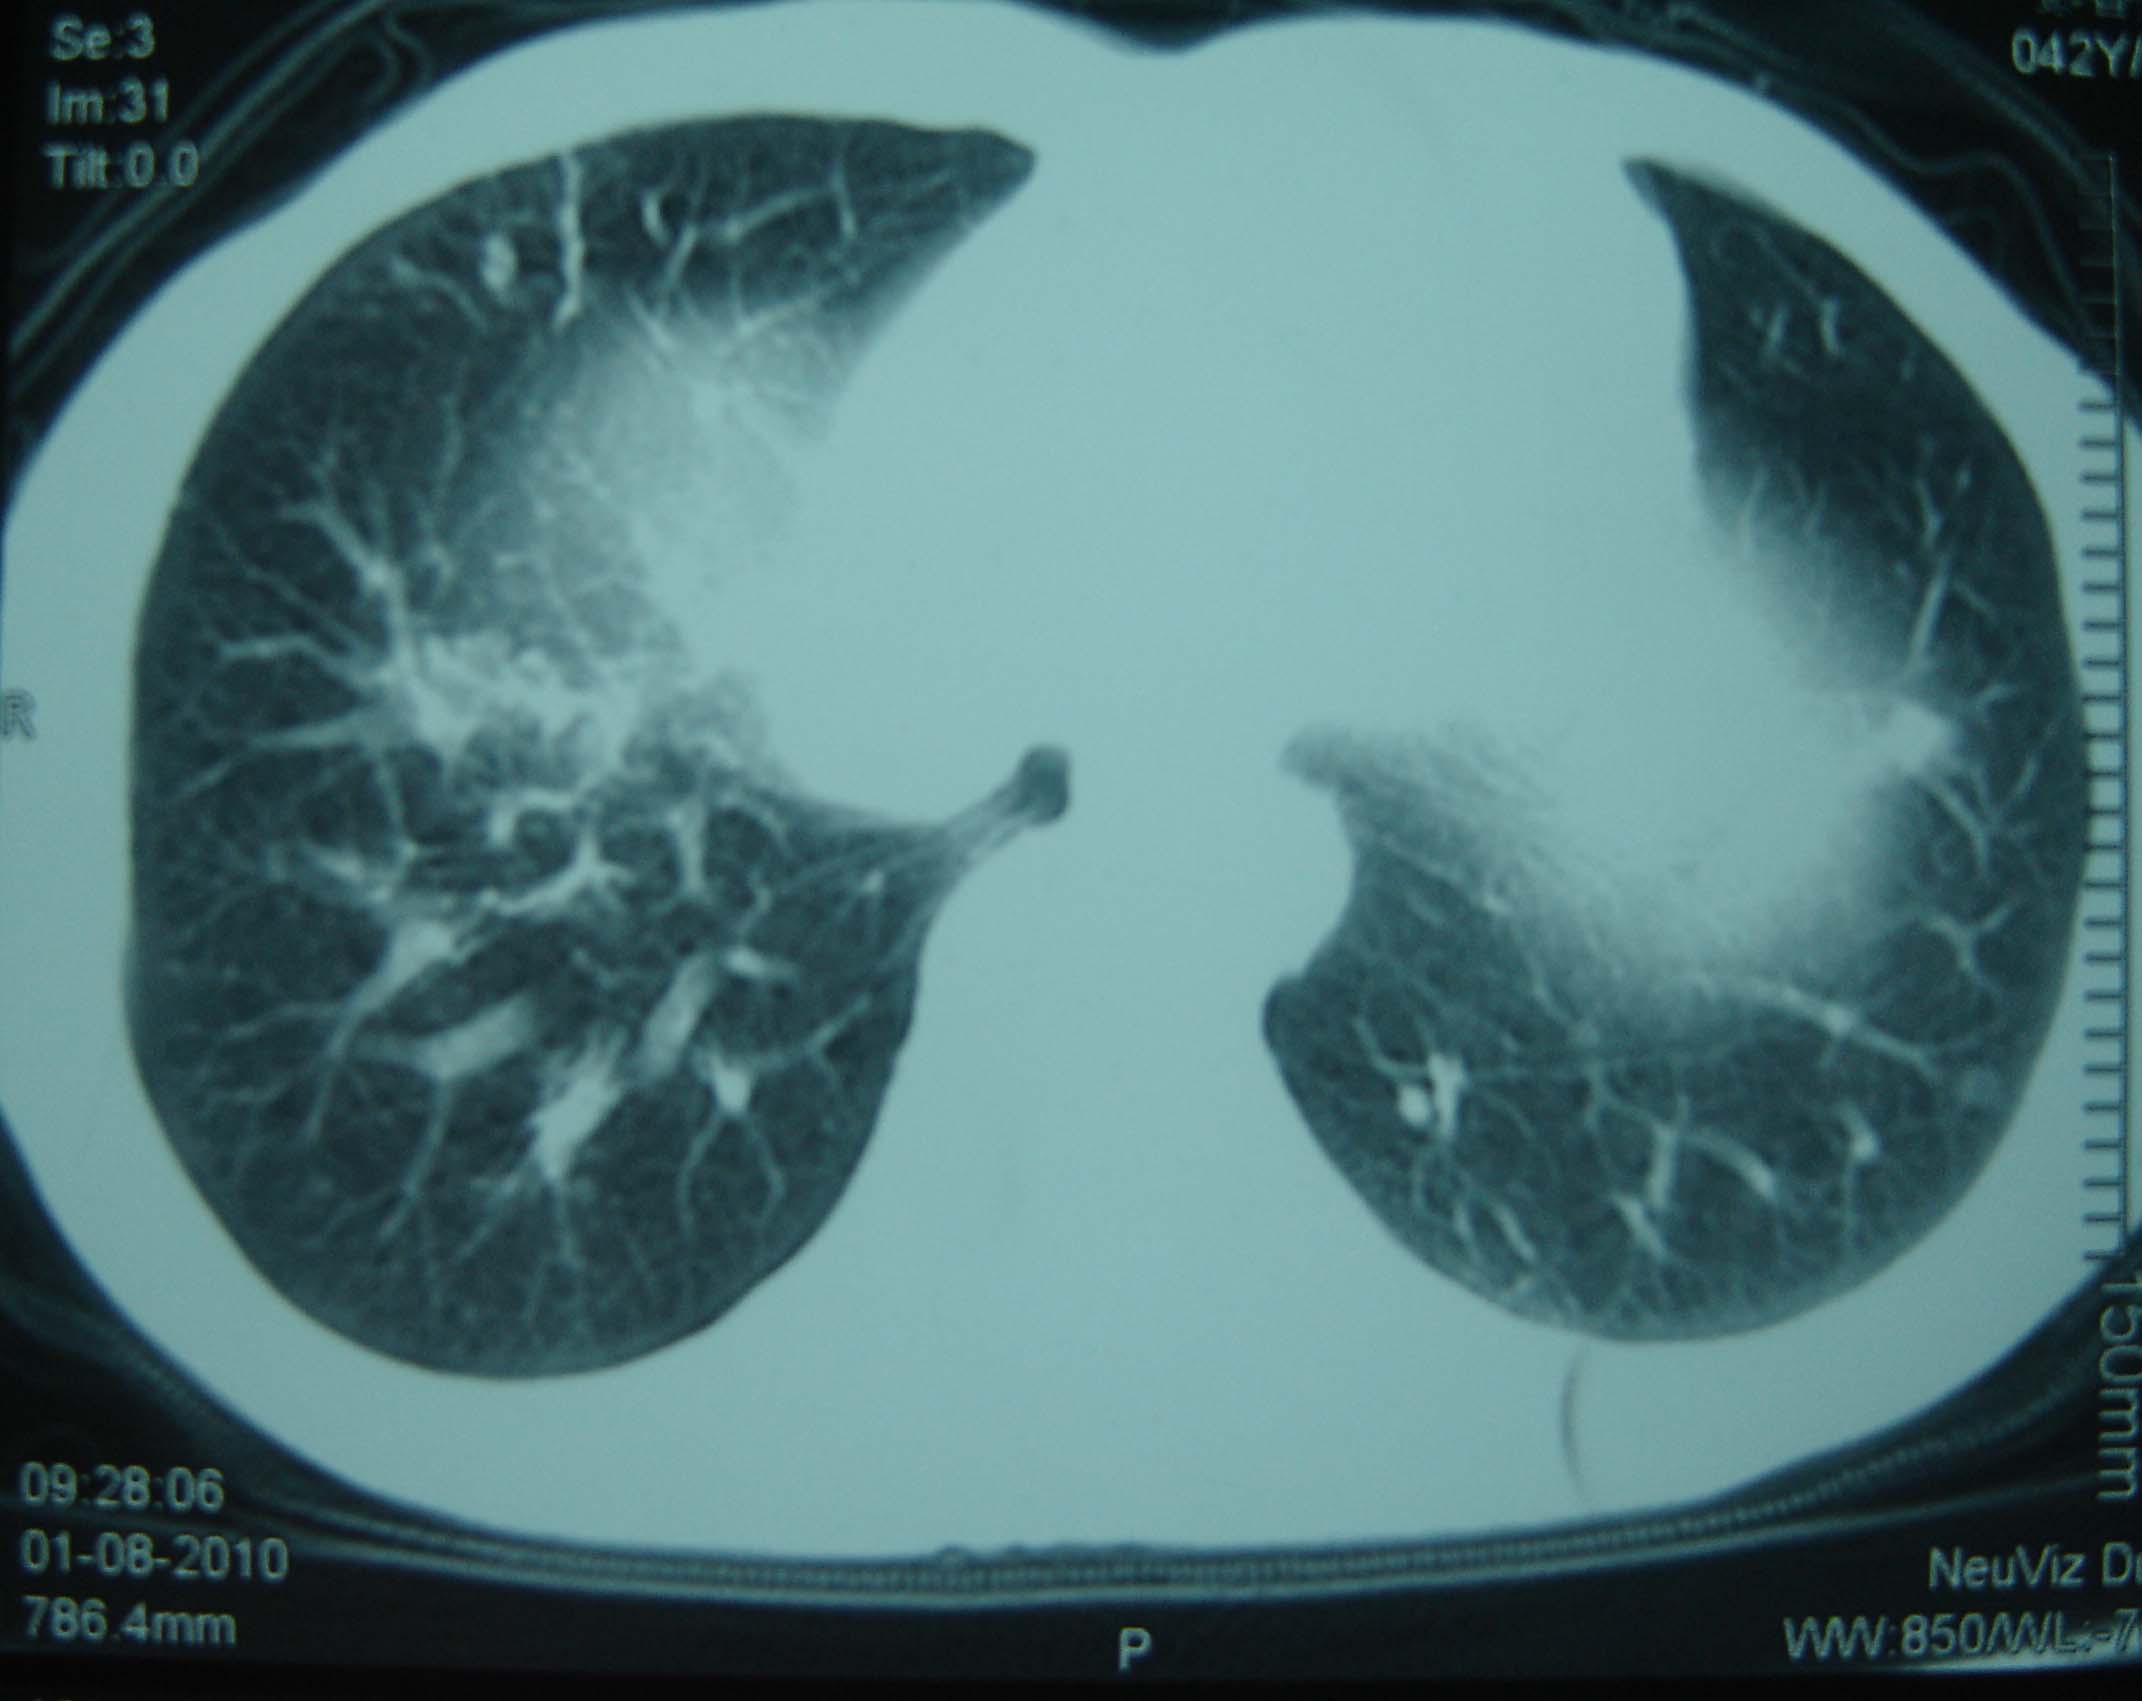

标题: CT25321:两肺多发结节 请会诊 [打印本页]

标题: CT25321:两肺多发结节 请会诊

男 、43岁,咳嗽胸痛,装修工,平时接触粉尘较多,有吸烟史10多年,纤维支气管镜检查未发现异常,胃镜、腹部b超检查亦未发现异常,颈部淋巴结活检未发现肿瘤细胞。

不能排除转移,如果不能找到原发灶,只有短期随访。

结节病?转移瘤?

1)考虑双肺及胸膜多发性转移瘤。2)肺气肿。